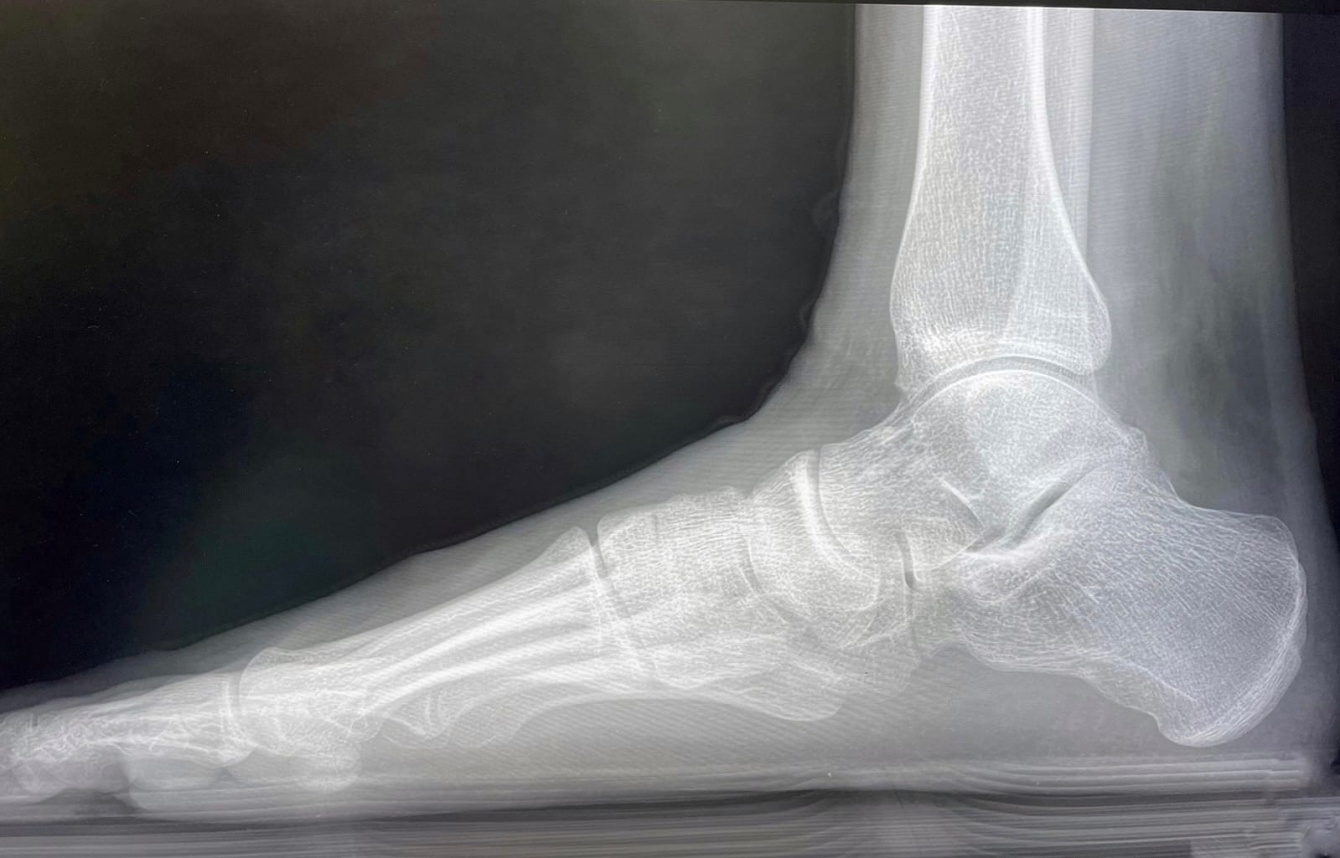

«Основная нагрузка пришлась на Центр травматологии и ортопедии. 189 пациентов принято в травмпункте, 24 из них госпитализировано, проведено 11 операций в стационаре. Частая причина обращений — «уличные» травмы»,